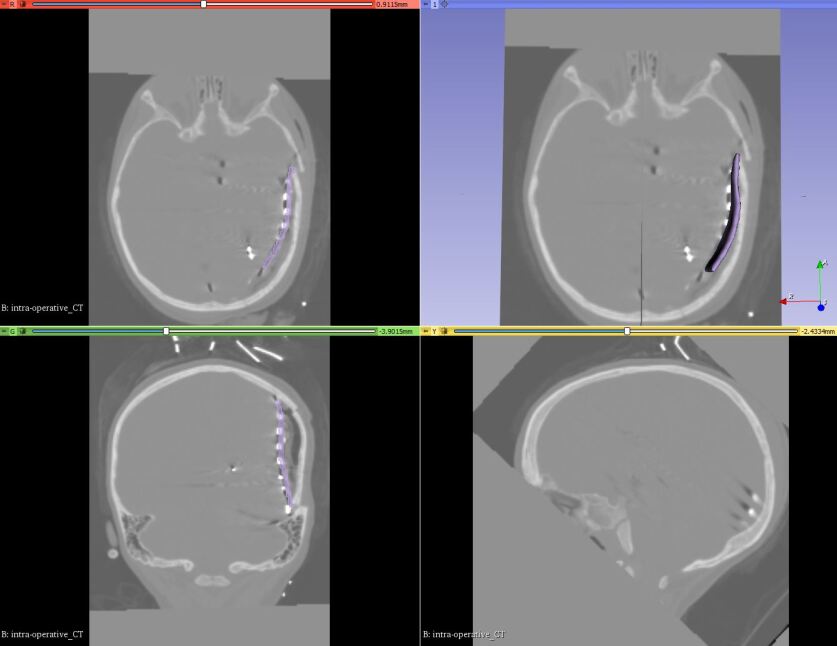

Refer to caption

Figure 5: 3D electrode sheet model overlaid with postoperative CT in axial, sagittal, coronal and 3D window within 3D Slicer

2.2.4 Generating an electrode sheet model:

ECoG strip and grid electrodes are typically composed of an array of platinum electrodes embedded into a sheet of a silastic material. Our automated procedure for reconstructing the electrode sheet geometry from the postoperative CT image is as follows: (1) extract electrode locations from postoperative CT image; and (2) create the electrode sheet model. In step 1, we extract the electrode coordinates from the segmented electrode volume (image set containing electrode segmentations) using our procedure implemented as a 3D Slicer module “Electrodes To Markups”. The postoperative (post-implantation) electrode positions were extracted (via segmentation) from the rigidly registered CT image to the preoperative MRI. The steps involved in extracting electrode locations using our procedure are as follows: (1) create a binary label volume from segmented electrode volume using auto thresholding; (2) split the binary label volume to individual segments corresponding to each electrode; and (3) add a point at the centroid of each electrode segment. The conversion from segmented electrode volume to binary label volume (step (1)) is performed using PolySeg [30], a software library that provides automatic conversions between different geometry representations (e.g., label map, surface) [30]. Splitting the binary label volume (step (2)) is performed using “split island into segments” and then “segment statistics” of segment editor effect module (step (3)) is used to get the centroids (centre of mass of the segment) [30]. In step 2, we used electrode locations to create an electrode sheet model by means of PolyData algorithm [31], which creates a triangulated surface. We then used delaunay method to construct an electrode sheet model based on triangulated surface [32].

Figure 7: Mean conductivity of the deformed model based on image data deformed by implantation of electrodes shown in axial, sagittal and coronal view overlaid with deformed MRI and 3D brain model in 3D window within 3D Slicer. The current dipole moment vector is denoted by the pink line with two fiducial points. The electrode sheet is denoted by the purple color.

Figure 8: Electric potential in the brain generated by a current dipole predicted by the deformed model based on image data deformed by implantation of electrodes. The current dipole moment vector is denoted by the pink line with two fiducial points. The electrode sheet model is denoted by the purple color.

We demonstrate the application of our framework by solving an iEEG forward problem. We solved the iEEG forward problem with a current dipole source using the deformed image data with the actual electrode locations. We put a dipole in the gray matter of the brain with a dipole moment of 100 µAmm to replicate a current dipole set up by cortical neurons. Fig. 7 shows mean conductivity of the deformed model based on image data deformed by implantation of electrodes. Fig. 8 shows the predicted distribution of electric potential within the brain computed using the model based on the deformed image data with the actual electrode positions. We used deformed image data with actual electrode positions to avoid the error introduced by using incorrect tissue geometry. As discussed in our previous study [23], the correct geometry can reduce the effect of inaccuracy of source localization.